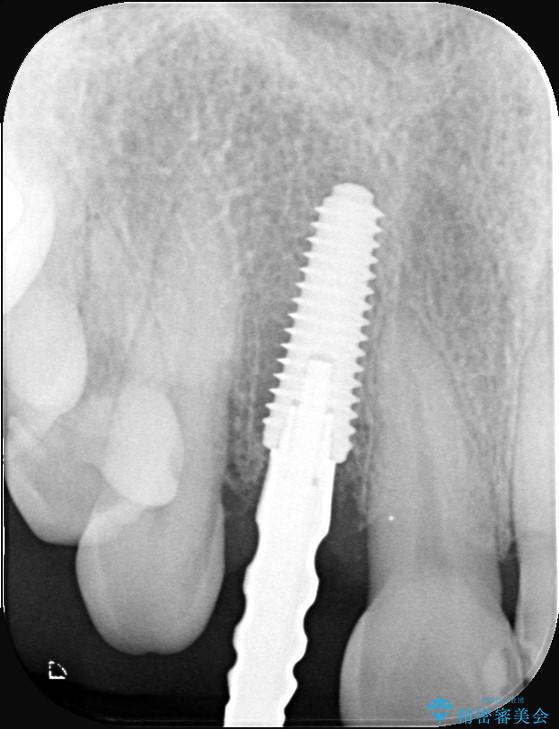

インプラント治療は、低侵襲で短期間に行える「抜歯即時インプラント治療」を選択しました。

この方法は、抜歯したその日にインプラントを埋入し、手術が1回で済むのが大きな特徴です。

治療期間も短く、抜歯からわずか3か月でオールセラミッククラウンを装着することができます。